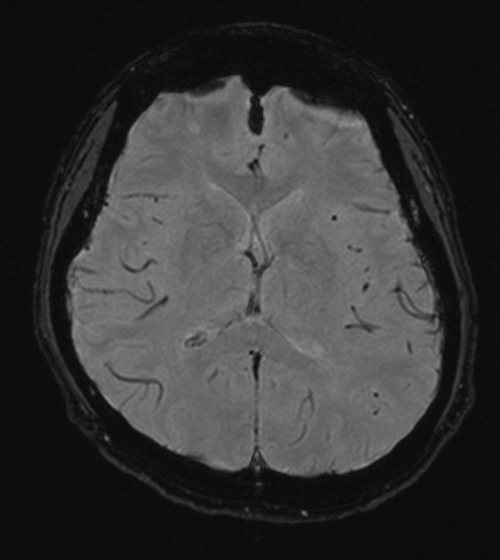

| 撮影可能な部位 | 頭部、脊椎、乳腺、腹部、骨盤部、関節など 全身領域 |

頭部MRI検査において、脳萎縮評価システムVSRADを用いた解析も行

っております。

MRI検査依頼書(PDF)当院で撮影したMRI画像